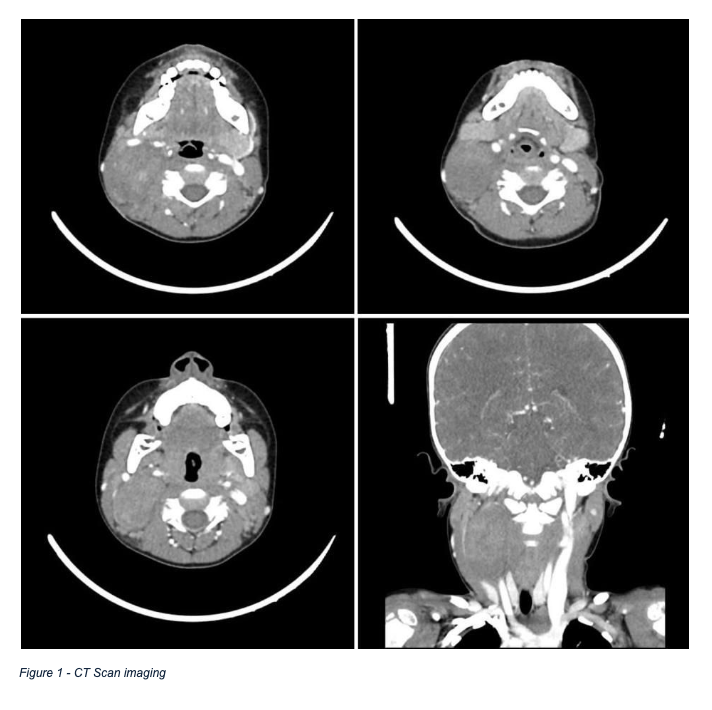

Ganglioneuroblastomas are commonly found in the extracranial region but in the head and neck region it is very rare disease. For patient evaluation diagnostic modalities like CT scan with contrast, MRI and fine-needle aspiration biopsy (FNAB) can help but the accuracy for definitive diagnosis is very limited. In this report we present the case of a 4-year-old male who presented with a neck mass which was slow-growing, along with multiple enlarged cervical lymph nodes. His workup raised a suspicion for ganglioneuroblastoma, which was later confirmed histopathologically. The patient was treated surgically which included resection of neck mass and cervical lymphnode dissection. No recurrence was observed at 6 months and 1-year follow-up. This report aims to contribute to existing literature by discussing diagnostic challenges, imaging findings, and surgical management of this rare tumor, providing insights into optimal clinical approaches.